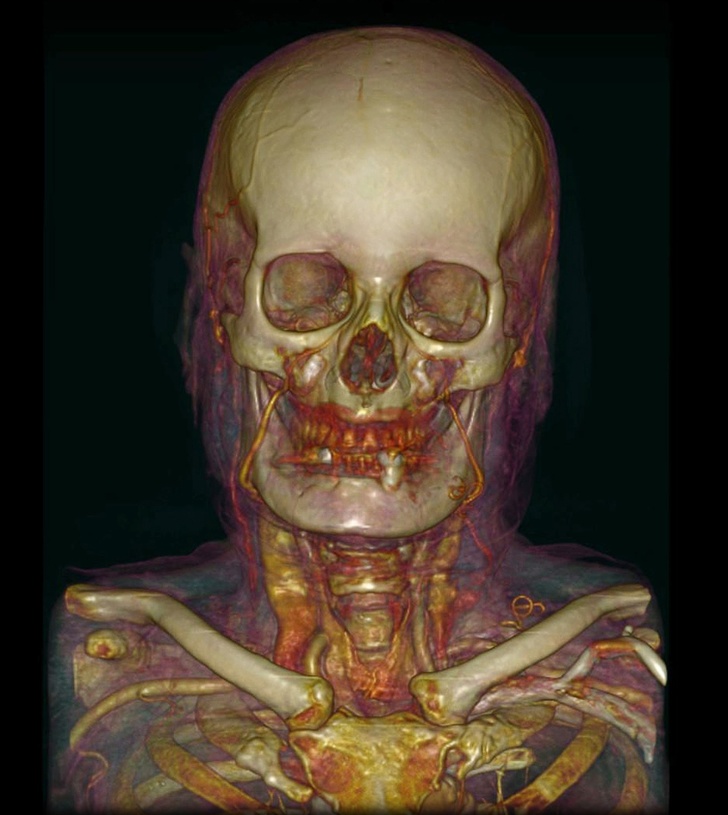

13. Комп'ютерна томографія черепа і судин